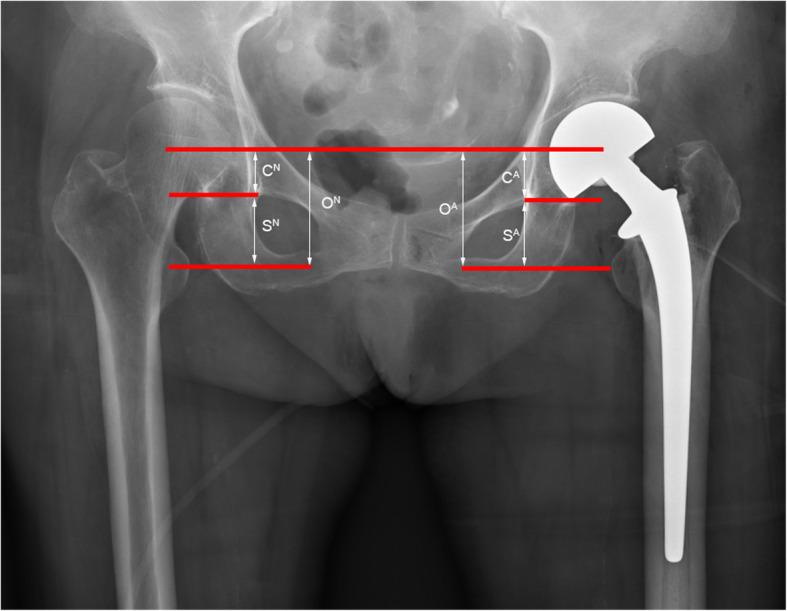

METHODS

Eighty-nine adult femur specimens were selected to observe the incidence of Osteo-line on the femur neck. From August 2015 to January 2019, a total of 278 patients who completed unilateral hip arthroplasty at the Third Hospital of Hebei Medical University were retrospectively included. Patients who accepted osteotomy via Osteo-line on the femur neck were defined as the experimental group (n = 139), and patients who accepted osteotomy via traditional method (The femoral distance 1.5 cm above the trochanter was retained for osteotomy by visual inspection.) were defined as the control group (n = 139). According to the postoperative pelvic X-ray, Photoshop was used to evaluate the leg length discrepancy (LLD) by the CFR-T-LT method.

选取89例成人股骨标本观察股骨颈骨线的发生率。回顾性纳入2015年8月至2019年1月在河北医科大学第三医院完成单侧髋关节置换术的278例患者。将采用股骨颈骨线截骨的患者定义为试验组(n = 139),将采用传统方法(通过肉眼观察在转子上方1.5 cm处保留股骨长度进行截骨)截骨的患者定义为对照组(n = 139)。根据术后骨盆X线片,使用Photoshop通过CFR-T-LT方法评估下肢长度差异(LLD)。